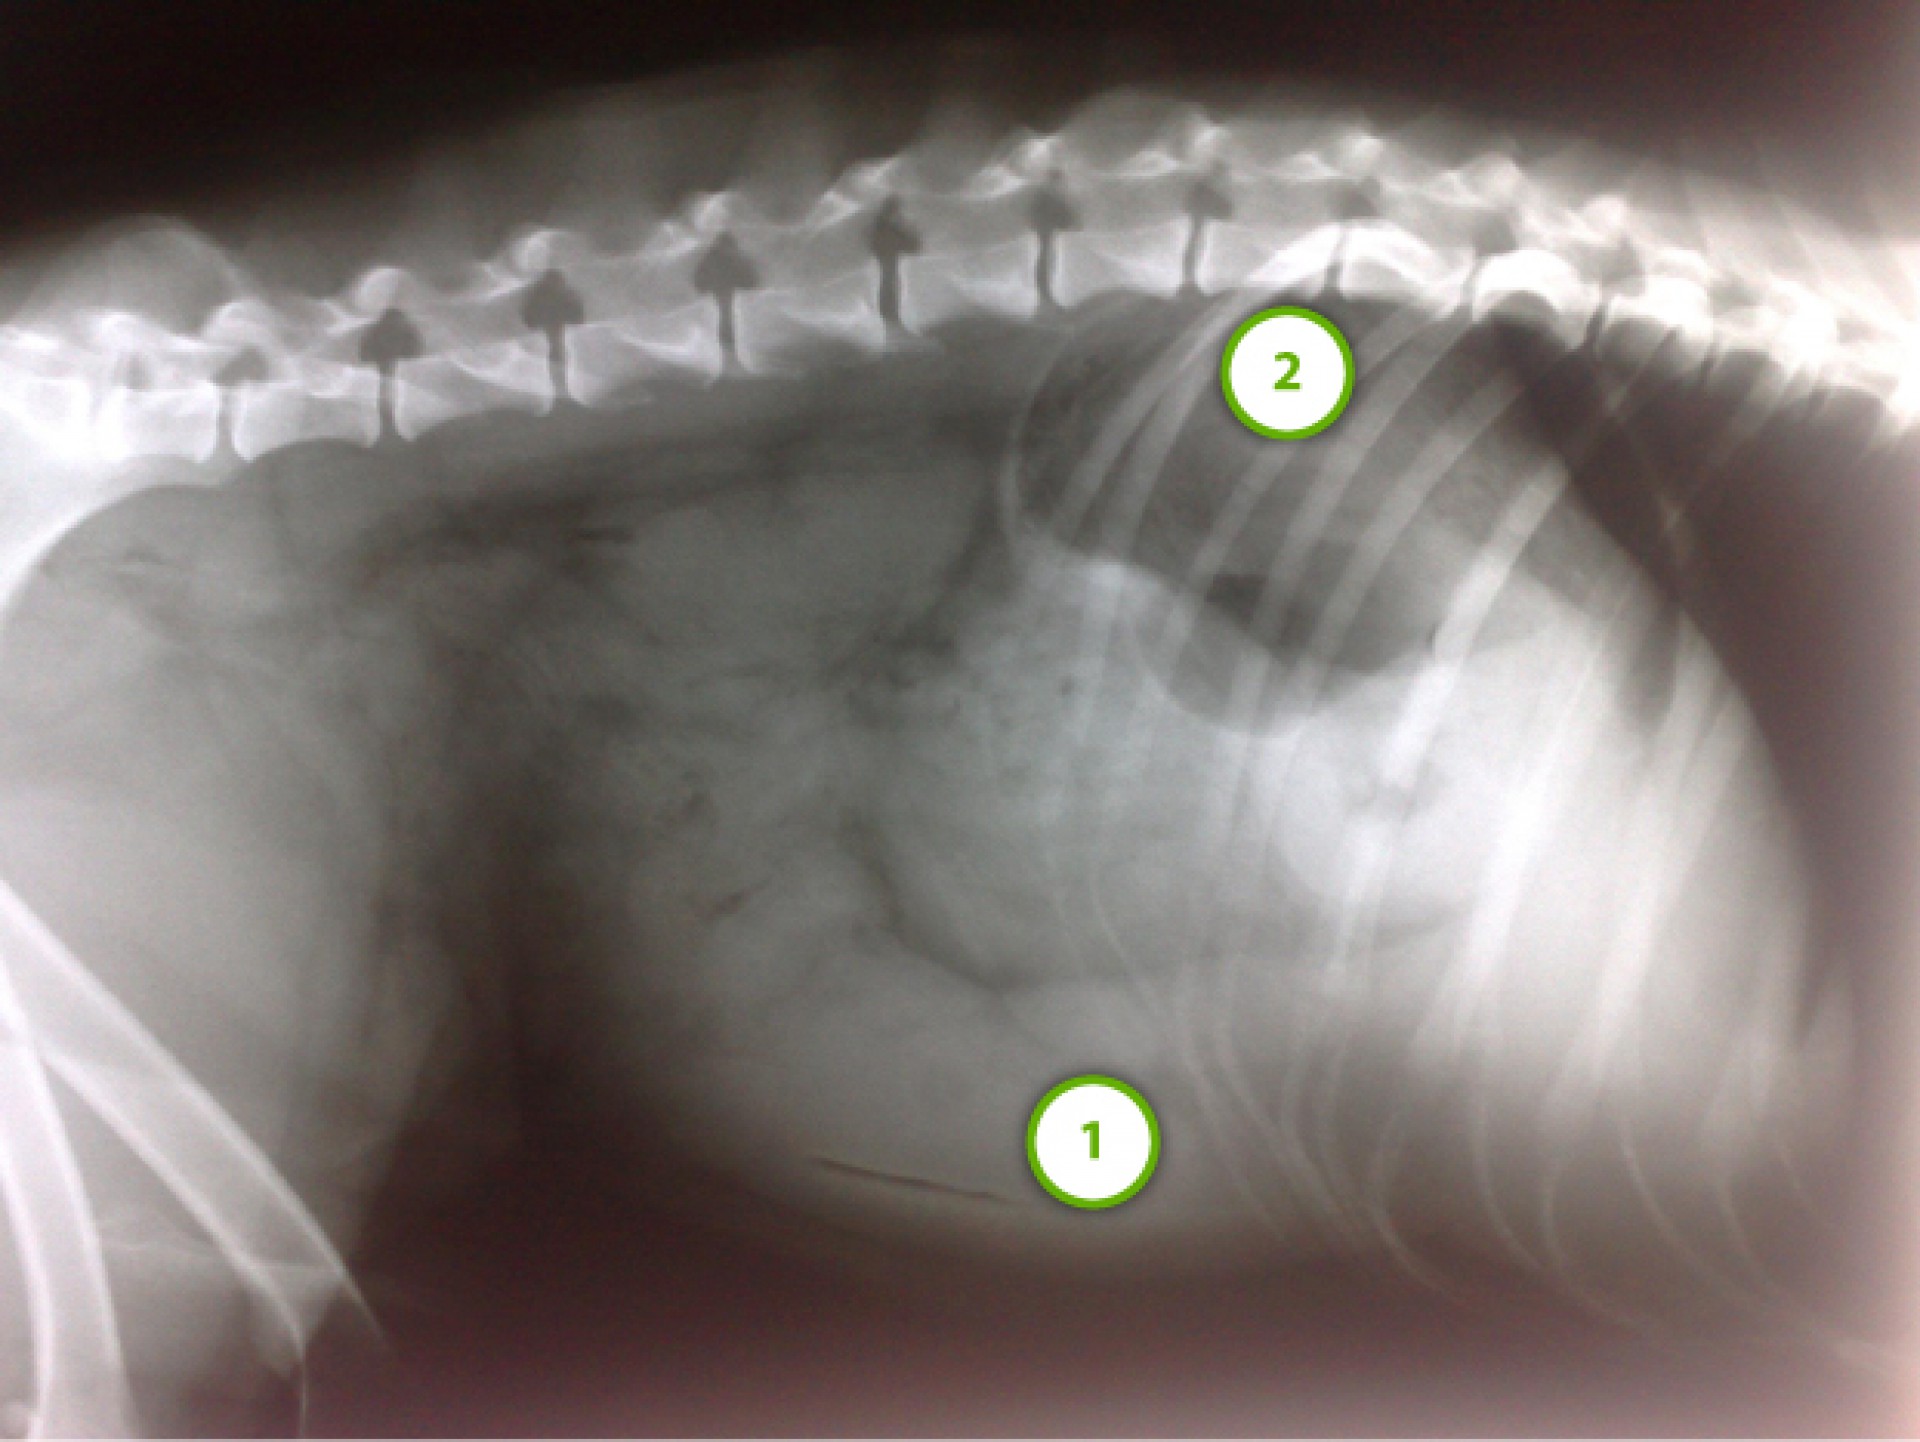

A láztalan kutya hasüregében jelentősen megnagyobbodott lép volt tapintható. Mivel babesiosis ellen már kezelték a lép megnagyobbodásának egyéb okát kellett keresnem, hát egy RTG felvételt készítettem.A felvételen a lép jelentős megnagyobbodása és helyzetváltozása volt látható.